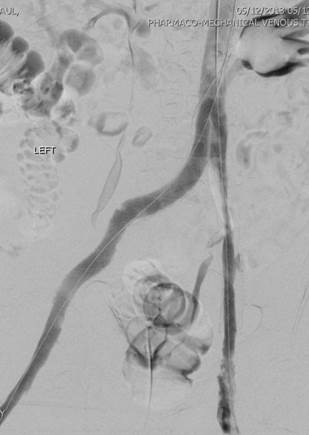

Venografía de la vena femoral tras trombectomía fármaco-mecánica (PMT) mediante la técnica Power Pulse Delivery (se usaron 15 ml de una solución de 50 mg de tPA  en 500 ml de solución salina natural) seguida por 2 pasadas con el catéter DVX de AngioJet.

Venografía en posición decúbito supino tras introducir 2 veces el catéter DVX de AngioJet. Vena ilíaca externa y vena femoral común del paciente. Estenosis severa de la vena ilíaca común.